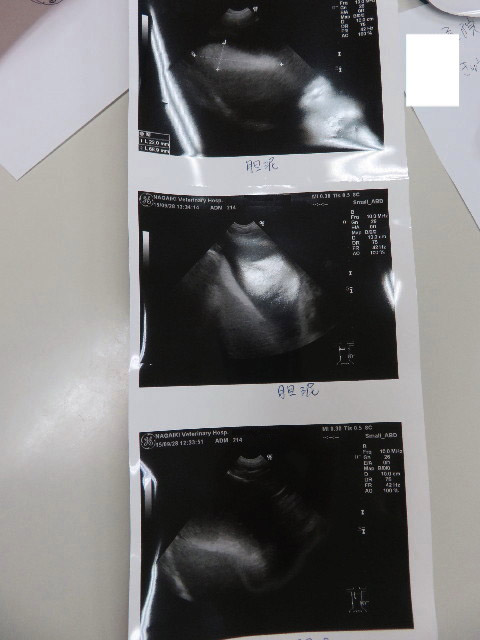

●エコー

○膀胱粘膜が肥厚し、かつ膀胱内部がギザギザのところも。

膀胱粘膜が炎症を起こしているという事は膀胱炎かもということで検尿しました。

結果、おしっこはキレイ(ほんの少し白血球がでている)ですが、結果としては膀胱炎による炎症でしょうとの事で消炎剤(バキソ10mg)を1日1カプセル14日飲むことに。(抗生剤は飲みません)

ひどくはなくて、これから注意が必要な膀胱炎とのことです。

※今までに、ひどい膀胱炎の最中にエコーをしたことがありますが、常に膀胱はきれいで、今回のように膀胱粘膜肥厚や、内部がギザギザになってしまったのは初めての事です(汗)

ということは、前回9月15日からわずか14日で、ひどくはないですが【23回目の膀胱炎】になってしまったということです(°_°)

○胆泥は、浮遊しているのは少なくなりましたが、底にたまっているのはあいかわらず。

胆泥は炭水化物と脂肪をひかえるとよいので、ケトン食に期待したいです。

今回のエコーの感じからすると、スカパールよりウルソのほうがよさそうなのでこのままウルソを継続します。

○腎臓は問題ありませんでした。